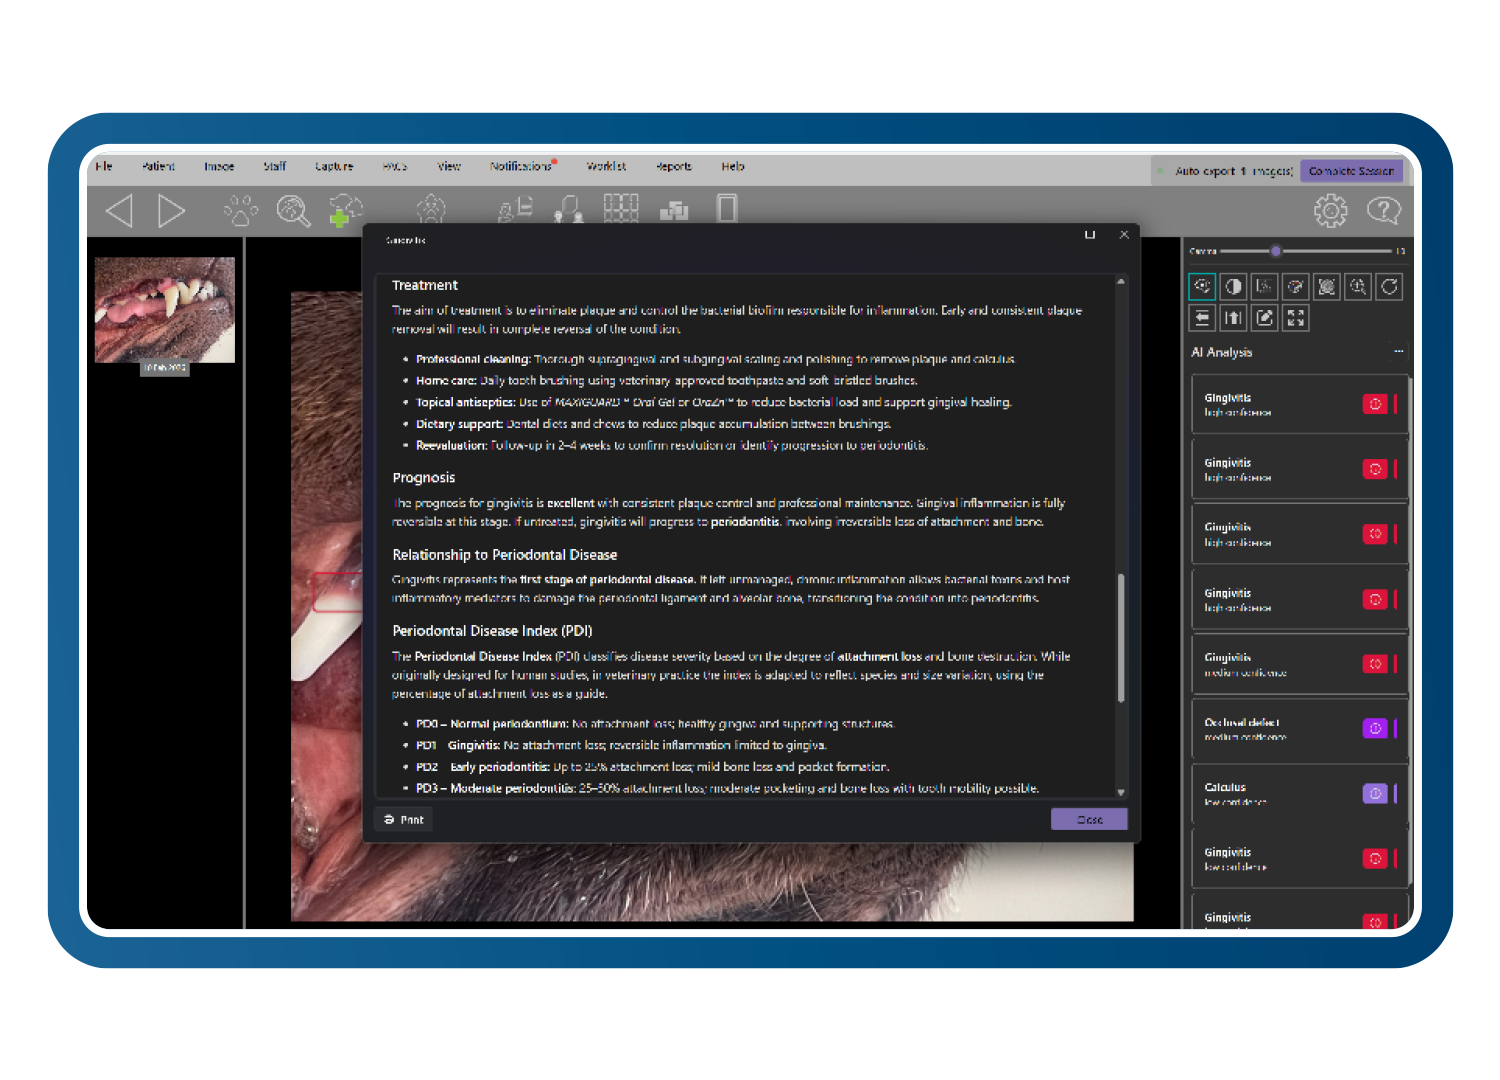

Clarity Question Lab (Aprendizaje y orientación clínica)

El laboratorio de preguntas de Clarity responde a cuestiones clínicas y procedimentales utilizando las directrices dentales de la WSAVA y material revisado por pares de especialistas en odontología veterinaria certificados por el consejo.

Las explicaciones instantáneas paso a paso respaldan el aprendizaje clínico y la coherencia, convirtiendo los casos cotidianos en momentos de enseñanza guiados según las mejores prácticas.